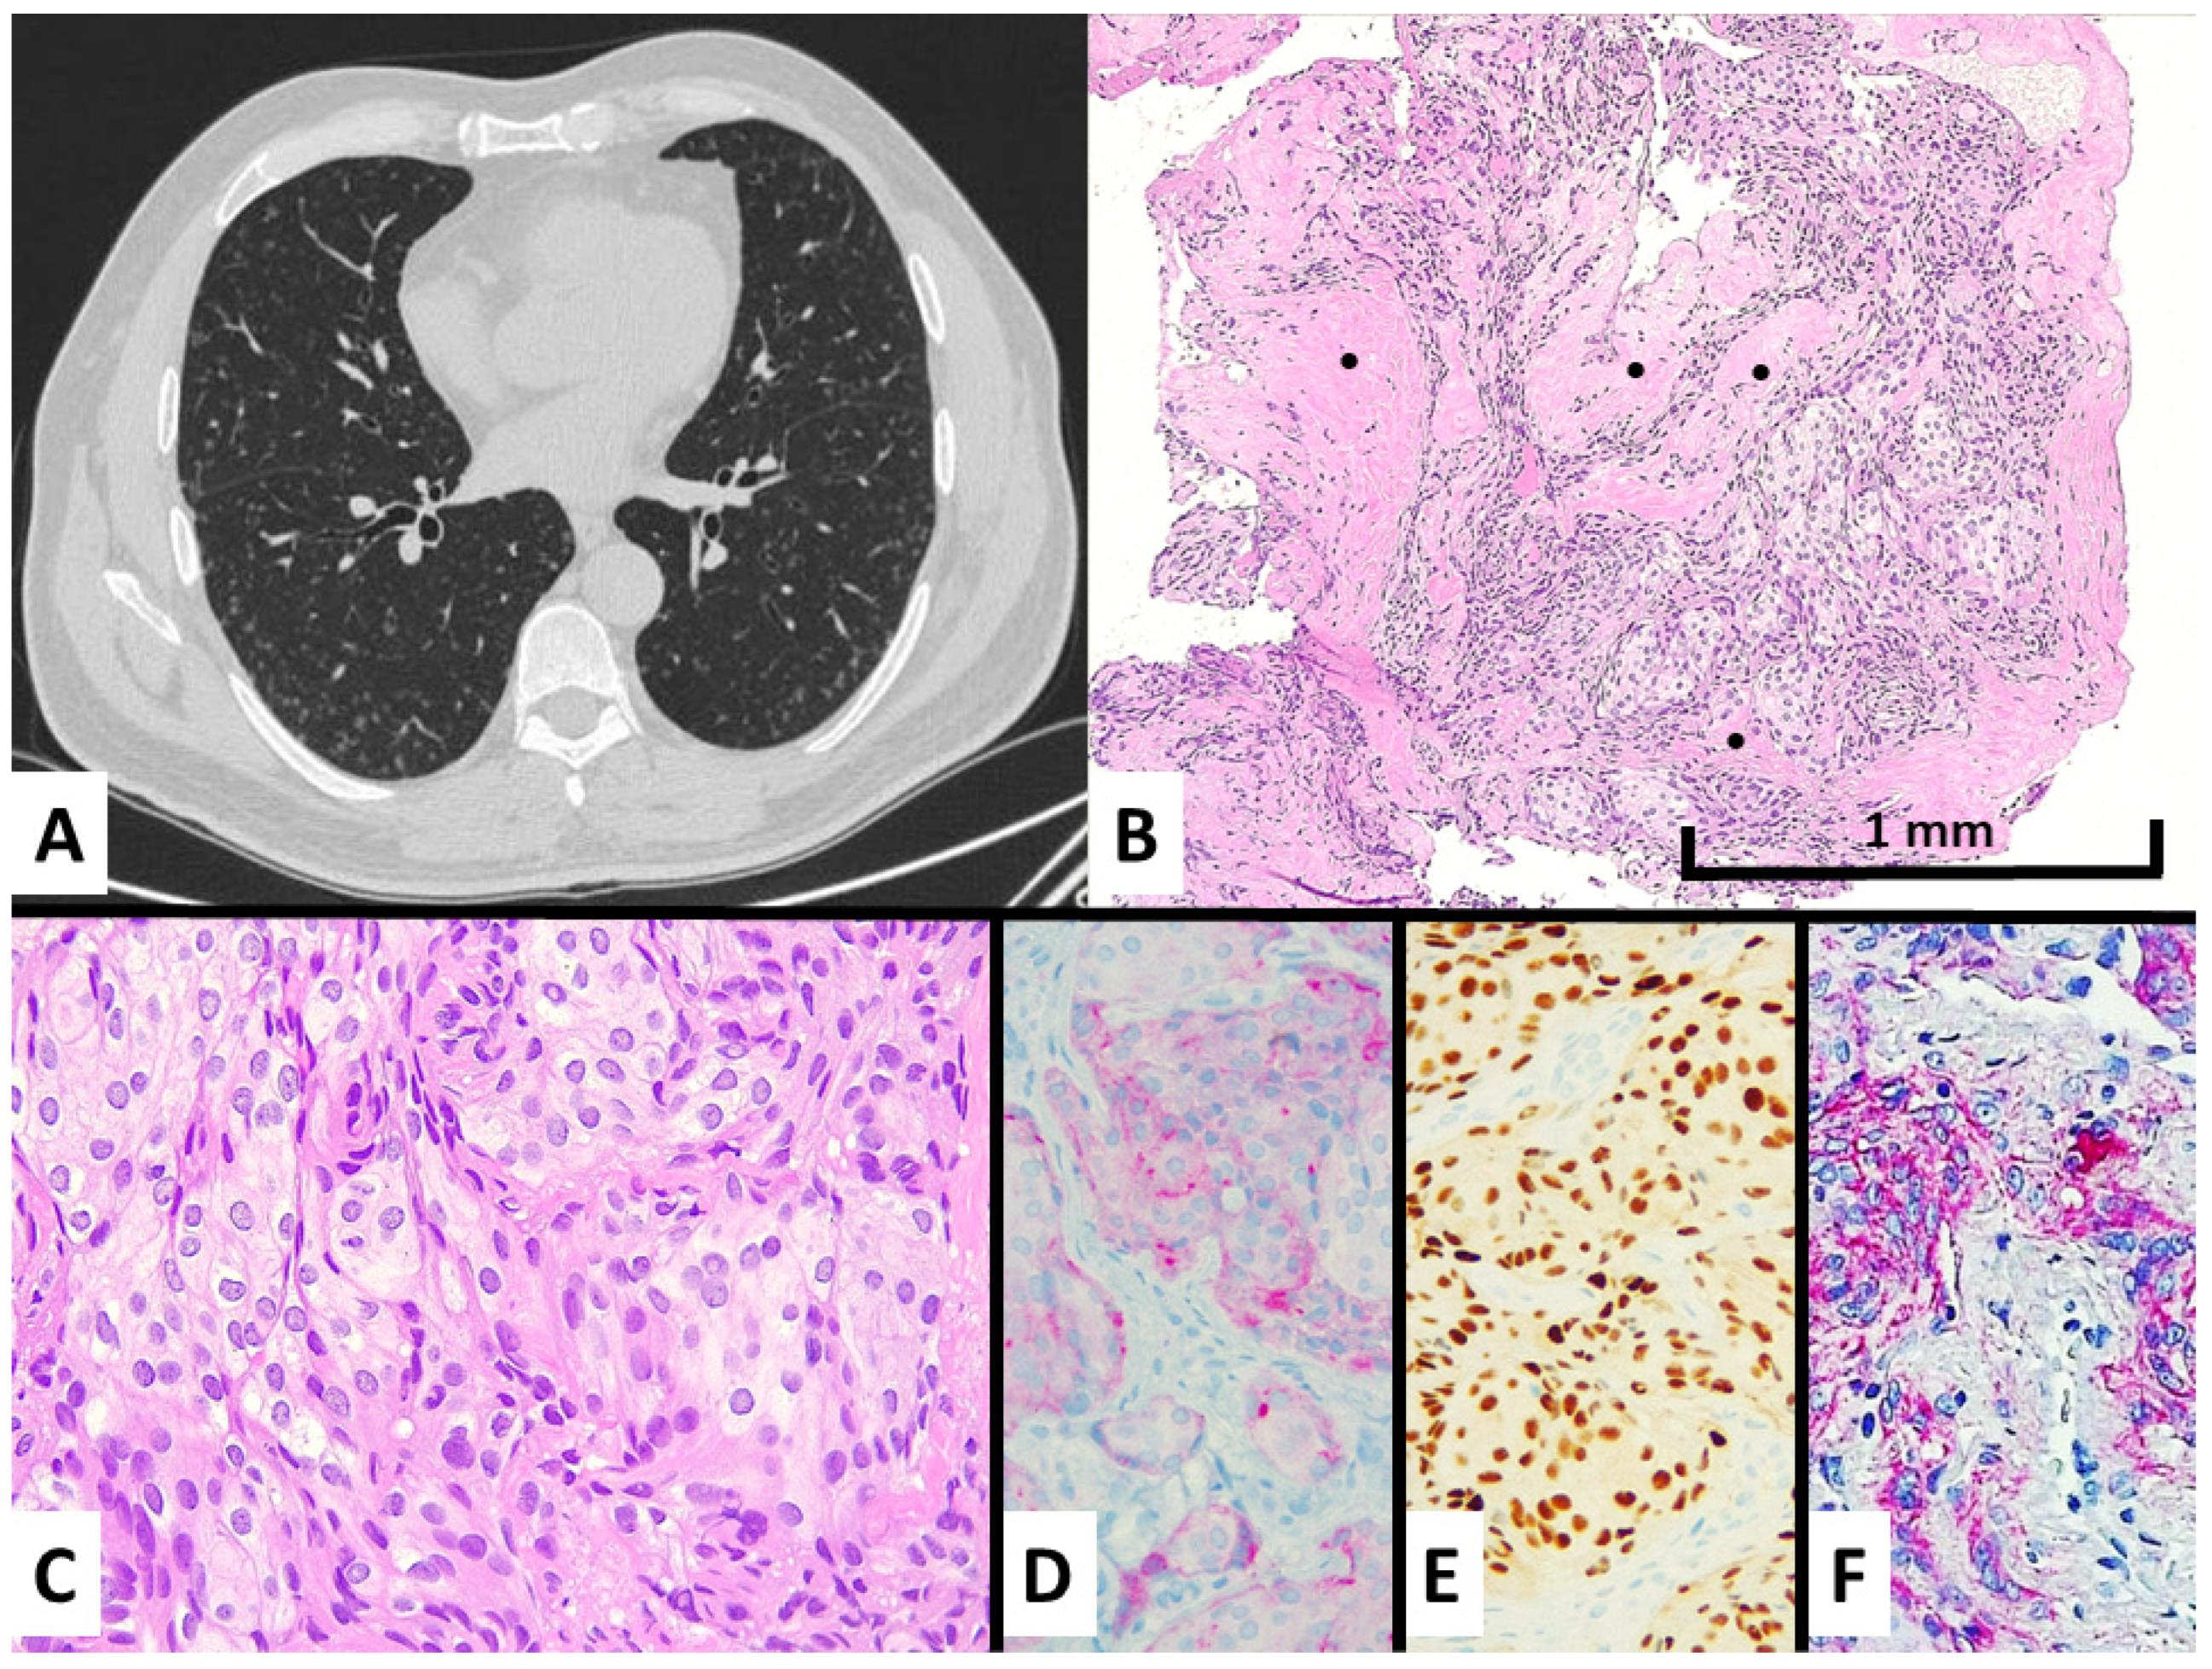

Figure 1.

Case #1 manifested with an incidental discovery of diffuse bilateral micronodules also showing ground glass appearance and central cavitation at chest CT scan (A) and spindled-to-epithelioid cell proliferation with intermingled fibrosis (see black dots) at transbronchial biopsy (B), hematoxylin–eosin magnification ×100, consisting of bland-looking cells with moderate cytoplasm lacking mitotic figures (C), hematoxylin–eosin stain magnification ×200. These cells showed a meningothelial cell differentiation by expressing EMA at cytoplasmic level (D), immunohistochemistry magnification ×200, progesterone receptors in the nuclei (E), immunohistochemistry magnification ×200, CD56 in cytoplasm and membrane (F), and immunohistochemistry magnification ×200.

The light microscope examination of the nodules showed a bland-looking proliferation of oval-to-spindle-shaped or epithelioid cells widening the interalveolar interstitial tissue, generally distributed around venules (Figure 1B,C and Figure 2D,E). Clusters of these neoplastic cells were vaguely arranged in whorl-like structures. Of note, central enlargement of alveolar airspaces surrounded by the proliferation of neoplastic cells seems to determine the cavitation/cystic changes centered in some nodules at CT scan (Figure 1A and Figure 2A). The cellular growth was often accompanied by variable amounts of collagenized fibrous tissue forming a scaffolding in both transbronchial and surgical samples. None of the four cases had any additional/alternative findings that could explain the formation of micronodules.

Immunohistochemically, the lesions showed consistent expression of epithelial membrane antigen (EMA), progesterone receptor, and CD56, whereas neuroendocrine, smooth muscle, melanocytic, vascular markers, CD10, cytokeratins, TTF1, and estrogen receptors were all negative (Figure 1D–F and Figure 2F,G). The proliferative index by Ki67 was low (~1%).